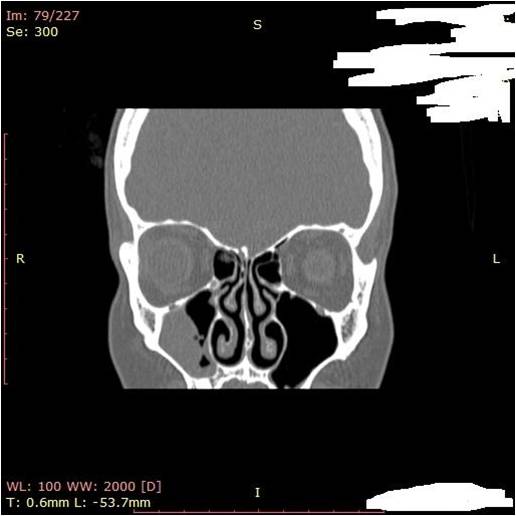

- компьютерная томография, оценка результатов которой позволяет установить точный диагноз и определить необходимый объем операции.

Рис. 2Предоперационная КТ PNS. В правой верхнечелюстной пазухе наблюдается куполообразная рентгеноконтрастность

Описанные жалобы не всегда являются признаком именно кисты, поэтому в большинстве случаев необходимы консультация оториноларинголога и выполнение томографии околоносовых пазух. Наиболее значимыми методами диагностики являются компьютерная или магнитно-резонансная томография придаточных пазух носа, позволяющие с точностью до миллиметра установить размер кисты, ее расположение в пазухе.